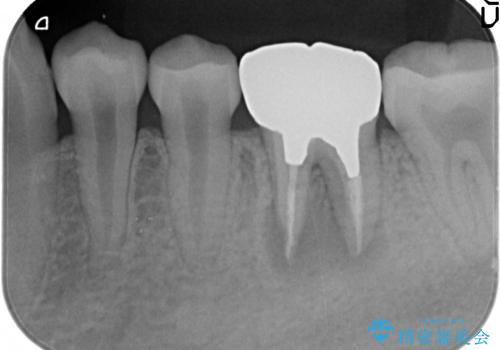

- 咬むと痛む左下6の歯を他院にて診てもらったところ抜歯しかないと言われたが、どうしても残したいと当院にいらっしゃった方の症例です。

検査の結果、根尖病変が大きくポケットも 10mm 以上ありましたが、マイクロ(顕微鏡)にて精査したところ歯根破折は認められなかったため、再根管治療を行いました。

咬合痛等の症状の緩解、根尖病変の縮小傾向、および深かったポケットが正常値まで改善したことを確認後、オールセラミッククラウンによる補綴を行いました。